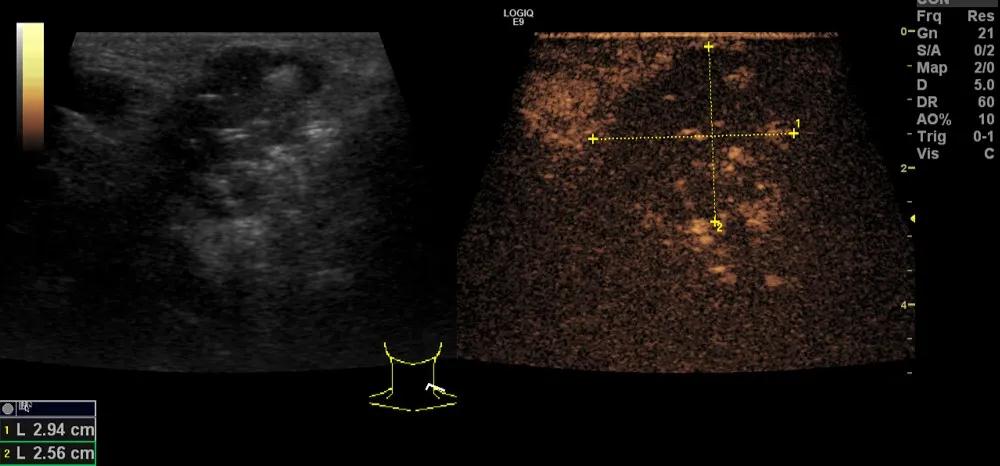

随后,徐栋教授进一步分享了五个临床实战病例,带来了更直观的热消融治疗经验。第一个病例是62岁肺癌患者,术后1年余发现双侧锁骨上淋巴结复发,侵犯神经,存在静脉回流、淋巴回流障碍,肿胀、疼痛非常明显。影像显示患者淋巴结边界不清、形态不规则,存在浸润,血流强化增强。由于患者在系统治疗后进展,且主要目的缓解症状、减瘤。局麻下行热消融术,从后向前逐层消融,热消融之后超声造影即刻评估显示完全充盈缺损,完全覆盖病灶。

(病例1图例)